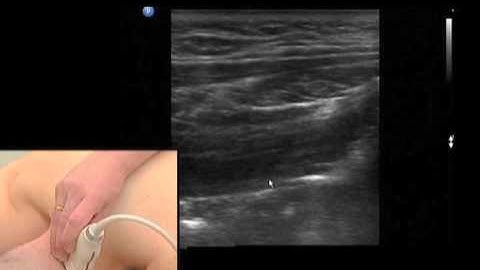

Scanning Technique: Occipital Nerve Block